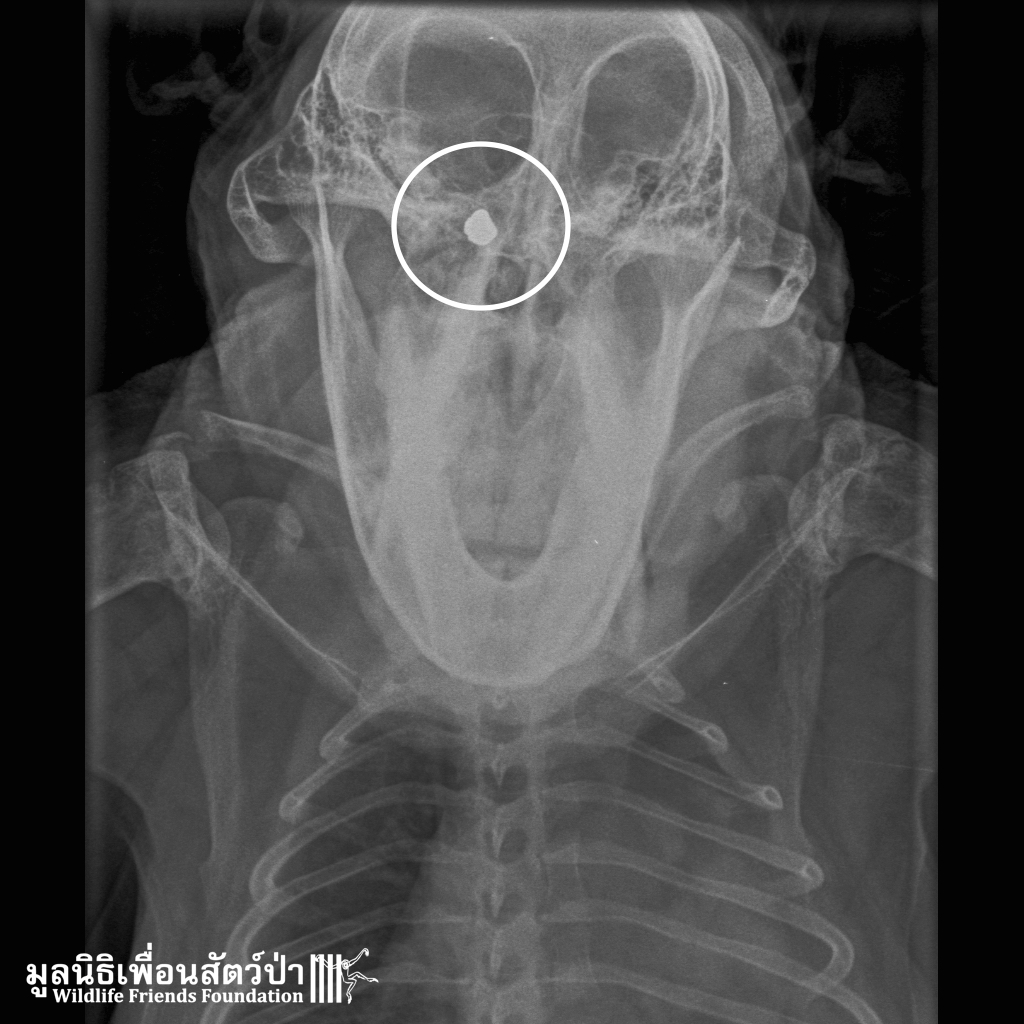

Late on Friday evening the WFFT Vet Team were called to attend an injured long-tailed macaque from an urban troop in Khao Wang, around 40km from the centre. The macaque had an injury to the face and had been found by locals walking about blindly.

On examining this male primate it was discovered he had an infected wound, which had caused swelling of his eyelids and closure of the eyes. X-ray confirmed that he had actually been shot between the eyes. The bullet had missed both eyes and time will tell whether it has damaged the optic nerve. The X-rays also showed that Frank, as he has been named, has suffered several bullet wounds in his life. Though he had been castrated this has obviously not resolved the human-animal conflict his troop is causing.